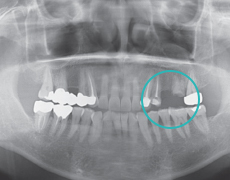

STEP 1

Pre-operative ExaminationExamine oral condition and establish treatment plan.